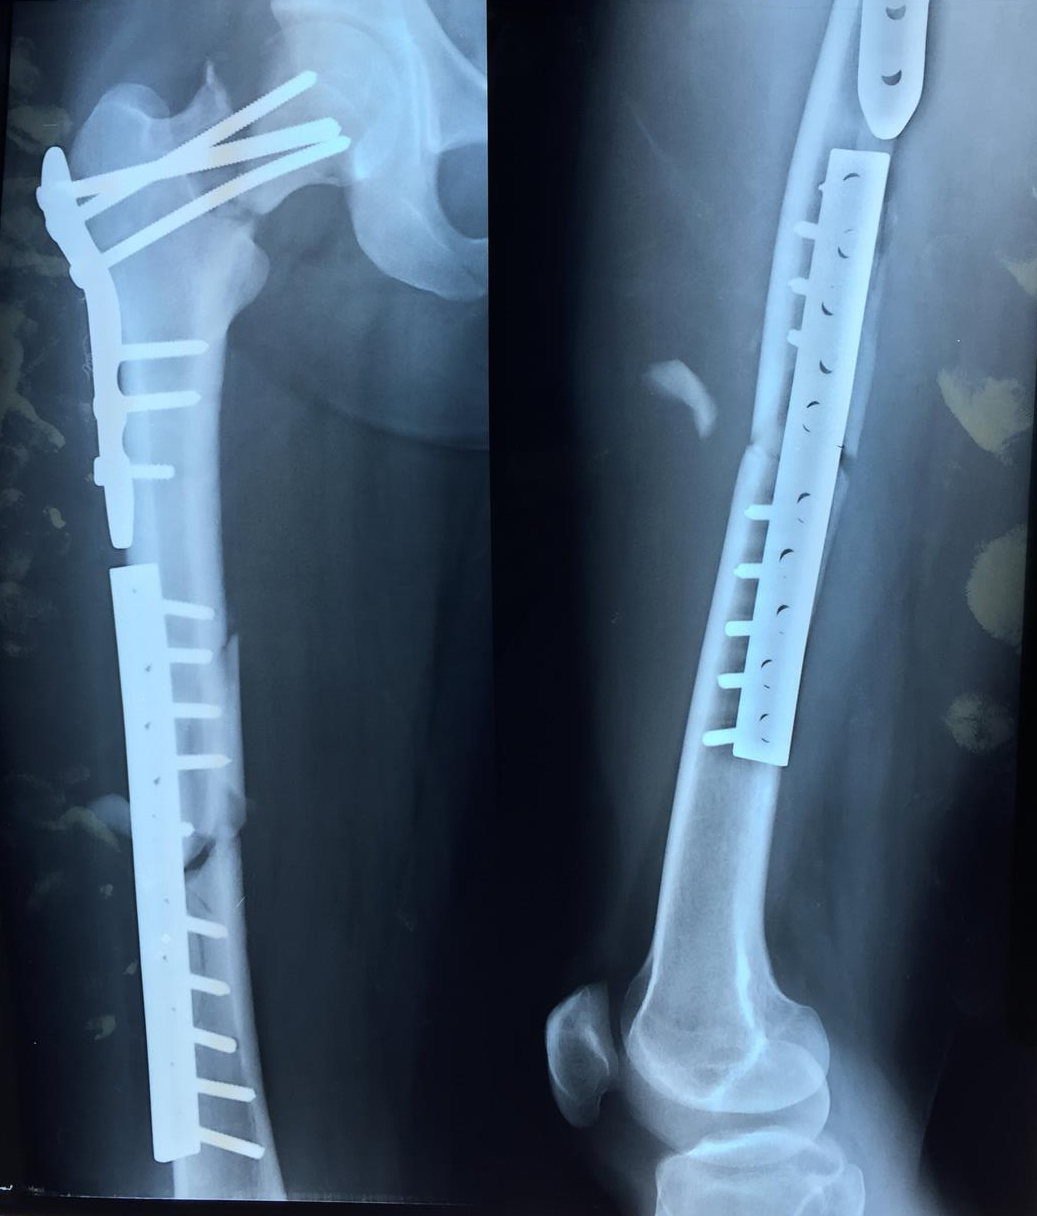

Femoral shaft fracture Open femoral fracture bone defect treated with Surgery Femoral Neck Fracture The garden classification of femoral neck fractures (fnf) dictates treatment via internal fixation or hip replacement, including. Should consider using the anterolateral approach and selective use of larger heads in the setting of a femoral neck fracture advantages improved functional hip scores and lower. Neck of femur fractures are typically caused either by low energy injuries (the most common type),. Surgery Femoral Neck Fracture.

Treatment of basicervical femoral neck fractures with proximal femoral Surgery Femoral Neck Fracture Neck of femur fractures are typically caused either by low energy injuries (the most common type), such as a fall in frail older patient, or high energy injuries, such as a road. How is a femoral neck fracture treated? Surgery is the most common treatment for a femoral neck fracture, though. Surgeons may recommend a full or partial hip replacement. Surgery Femoral Neck Fracture.